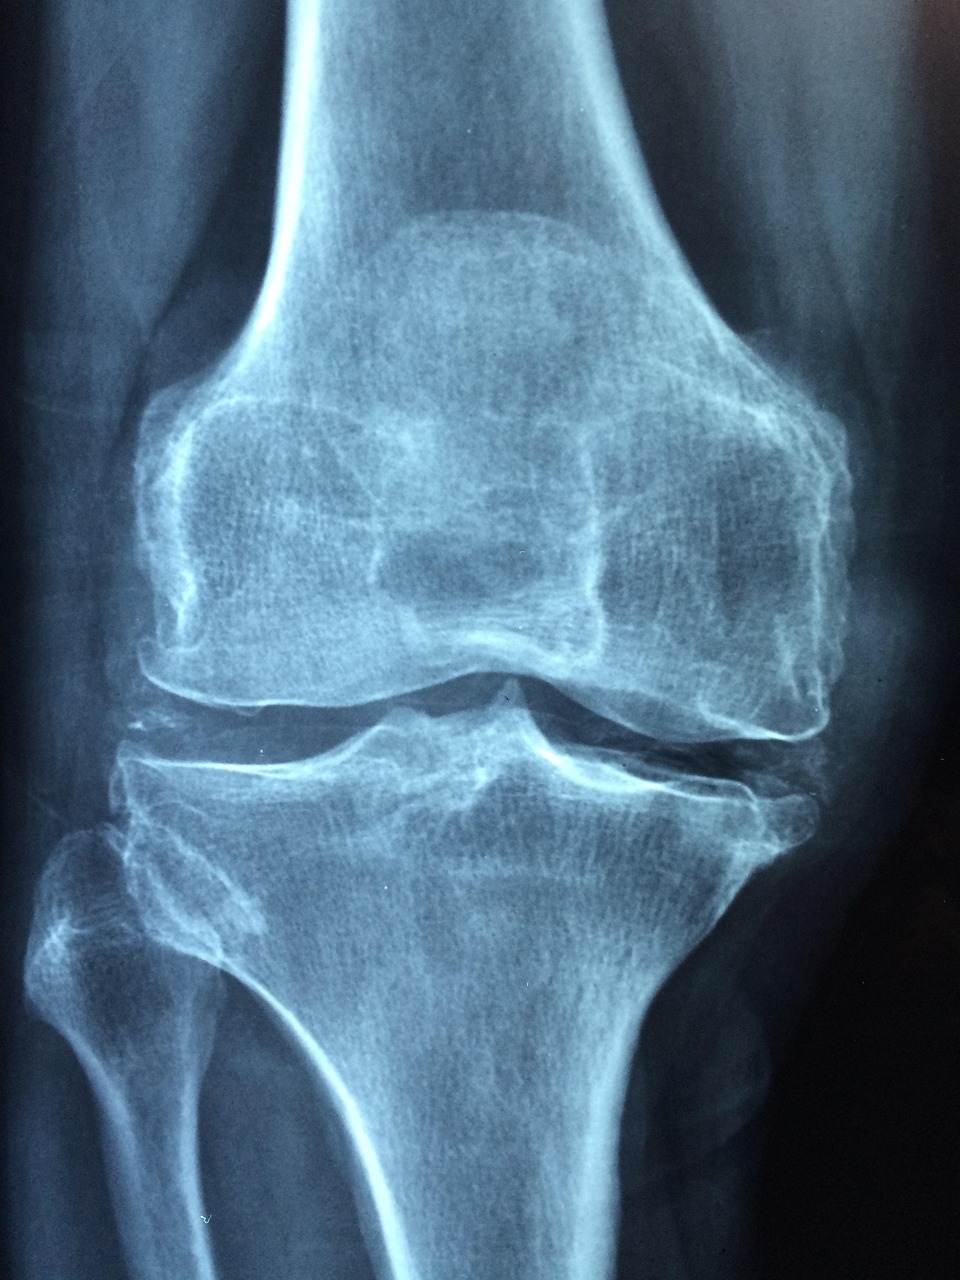

5. 실제 극복 사례 – 어떻게 회복했을까?

사례 A (52세 여성)

주사치료 1년 + 칼슘 식단 병행으로 T-score -3.0 → -2.2 회복

사례 B (45세 남성)

조기 발견 후 주 3회 운동 + 영양제 복용으로 골감소증 수준 회복

사례 C (66세 여성)

골절 이후 치료 중단 없이 2년간 관리하여 재골절 없이 유지 중

공통점은 “꾸준함”과 “전문 상담”이 핵심입니다.